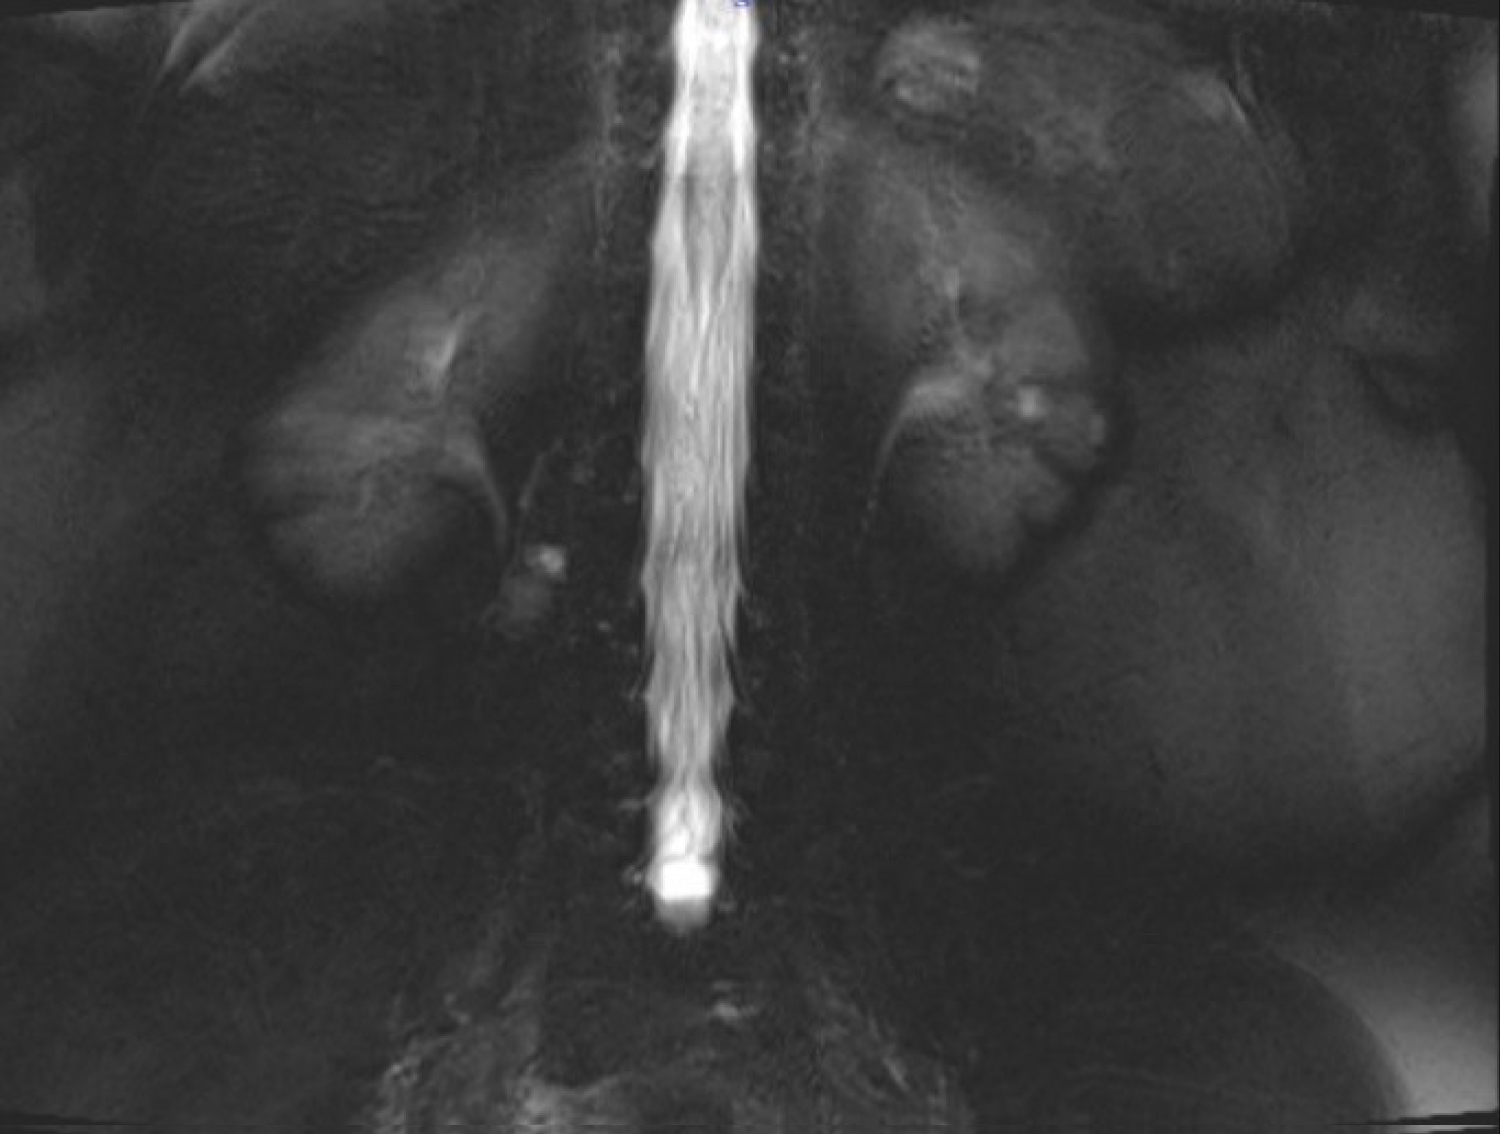

Magnetic resonance myelogram showed no cerebrospinal fluid flow obstruction (Figure 1). Careful evaluation of T1 weighted images showed a hypointense contrast-enhancing mass in the paravertebral muscle originating from the right lumbar (L) 3-4 facet joint (Figure 2). T2 weighted images showed a hyperintense mass in the same region (Figure 3).

Figure 1: Magnetic resonance myelogram. View Figure 1